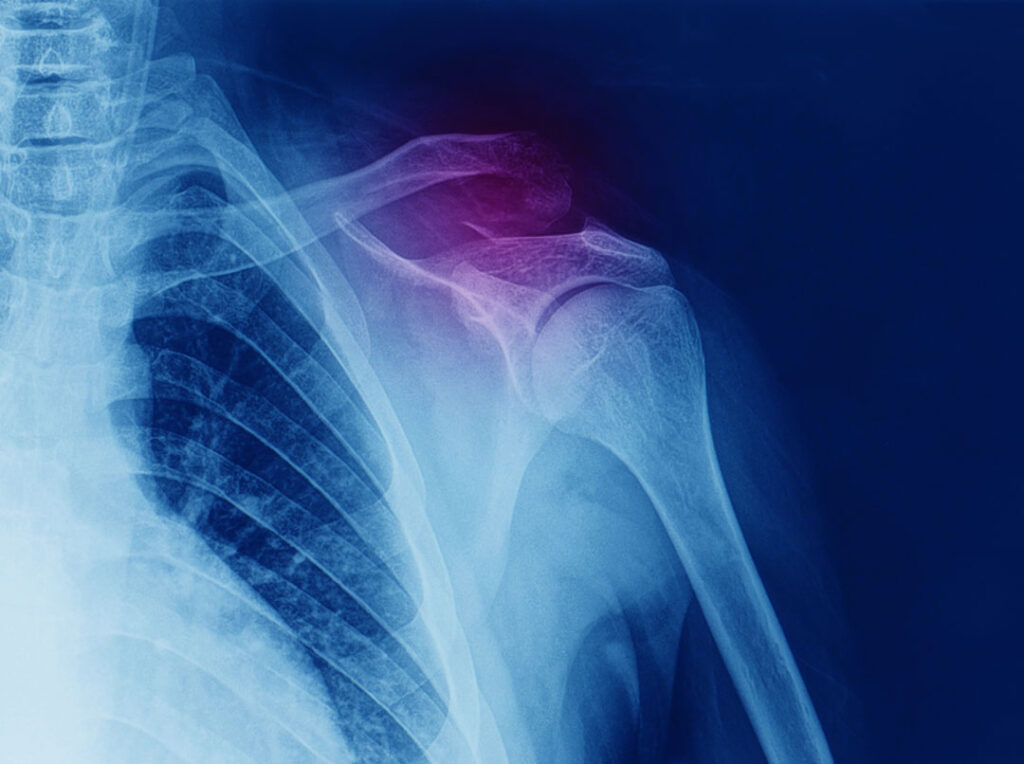

Suggest X-ray

Your collarbone and shoulder blade articulate together at the acromioclavicular joint, and the coracoclavicular and acromioclavicular ligaments help stabilise the joint. These ligaments are susceptible to injury and, when sprained or torn, can cause the joint to separate.

Symptoms of AC joint injury can vary. Commonly, people will have pain at the tip of their shoulder, and in the muscles that connect the shoulder to the neck like the upper trapezius. Pain is made worse with overhead use of your arm, reaching your arm across your body and the joint can feel unstable in this position. In severe AC joint dislocations, people will develop a ‘step deformity’ which looks like a prominent lump in the tip of the shoulder where the collar bone ends.

Choosing the right therapist starts with them being able to read your X-rays, clinical assessment to determine the appropriate treatment. The therapists at Action Rehab Hand Therapy Clinic are experienced in assessing and reading X-rays.